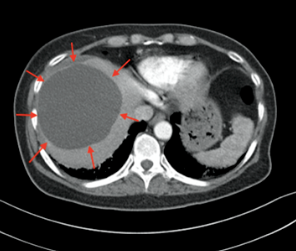

B型超声检查诊断肝囊肿具有敏感性高、无创伤、简便易行等优点,<1cm的囊肿也易检出,准确率达98%,而且能确定囊肿的性质、部位、大小、数目及累及肝脏的范围,为本病的首选检查方法。典型的超声表现是,肝脏上显示的圆形或椭圆形无回声区,部分在囊内可出现分隔;若有囊内出血、感染等,囊液可有高回声的光点,甚至在囊内可发现气泡,这时需结合患者临床症状综合判断。鉴别诊断是排除多囊肝、肝包虫病、肝脏黏液性囊腺瘤等。

肝囊肿